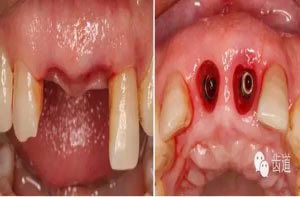

微創(chuàng)拔除根折牙

拔牙窩

探查唇側(cè)骨板(約齦下3-4mm)